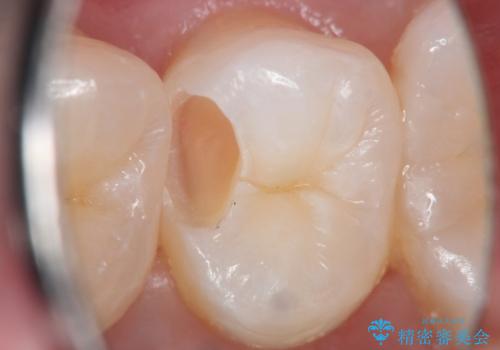

- 定期検診にてむし歯を認めたため、セラミックインレーにて修復を行いました。

e-max プレスインレーにて修復治療を行っているため適合性及び審美性の高い治療を行うことができます